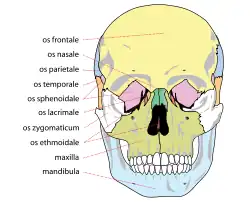

Commonly injured facial bones include the nasal bone (the nose), the maxilla (the bone that forms the upper jaw), and the mandible (the lower jaw). The mandible may be fractured at its symphysis, body, angle, ramus, and condyle.[4] The zygoma (cheekbone) and the frontal bone (forehead) are other sites for fractures.[13] Fractures may also occur in the bones of the palate and those that come together to form the orbit of the eye.

At the beginning of the 20th century, René Le Fort mapped typical locations for facial fractures; these are now known as Le Fort I, II, and III fractures (right).[7] Le Fort I fractures, also called Guérin or horizontal maxillary fractures,[14] involve the maxilla, separating it from the palate.[15] Le Fort II fractures, also called pyramidal fractures of the maxilla,[16] cross the nasal bones and the orbital rim.[15] Le Fort III fractures, also called craniofacial disjunction and transverse facial fractures,[17] cross the front of the maxilla and involve the lacrimal bone, the lamina papyracea, and the orbital floor, and often involve the ethmoid bone,[15] are the most serious.[18] Le Fort fractures, which account for 10–20% of facial fractures, are often associated with other serious injuries.[15] Le Fort made his classifications based on work with cadaver skulls, and the classification system has been criticized as imprecise and simplistic since most midface fractures involve a combination of Le Fort fractures.[15] Although most facial fractures do not follow the patterns described by Le Fort precisely, the system is still used to categorize injuries.[5]